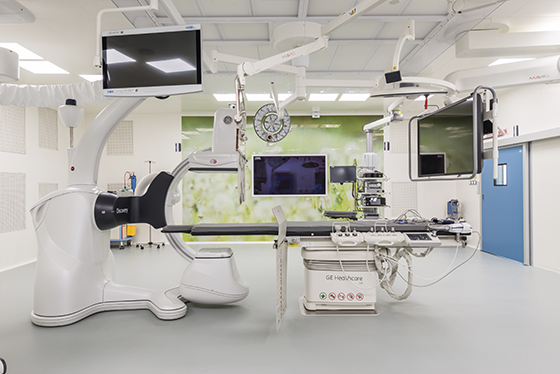

В институте онкологии Hadassah Medical Moscow создана специализированная группа профессионалов под руководством врача-онколога, к.м.н, директора отдела клинических исследований Утяшева И.А. Эти специалисты нацелены на исследование и лечение рака бронхов. Наша команда уделяет особое внимание инновационным методам лечения, стремясь обеспечить каждому пациенту максимально эффективный и безопасный терапевтический процесс, в полном соответствии с международными стандартами онкологической помощи.

Уникальность лечения болезни в Хадассе

В Hadassah Medical Moscow мы используем многоуровневый подход к диагностике, включая клинические, лабораторные и инструментальные методы исследований.

В клинике Hadassah Medical Moscow мы стремимся к индивидуализации лечебного процесса, используя многофакторный подход и современные медицинские технологии.

В центре внимания нашей клиники — создание персонализированных планов лечения, опирающихся на каждую конкретную клиническую картину и потребности пациента, с использованием междисциплинарного подхода для обеспечения оптимальных результатов и качества жизни пациентов.

В Hadassah Medical Moscow мы прилагаем все усилия, чтобы обеспечить пациентам самые передовые и эффективные методы лечения. Наши специалисты регулярно повышают свою квалификацию и следят за инновациями в онкологии, чтобы внедрять их в практику лечения.

В институте онкологии Hadassah Medical Moscow мы собрали команду ведущих специалистов, обладающих международным опытом и знаниями последних инноваций в области онкологии.

Благодаря современному оборудованию, передовым методикам лечения и индивидуализированному подходу, мы стремимся обеспечить каждому пациенту оптимальные условия для восстановления здоровья. Пациенты и их близкие могут рассчитывать на полное внимание, заботу и поддержку со стороны нашего медицинского персонала на каждом этапе диагностики, лечения и реабилитации.